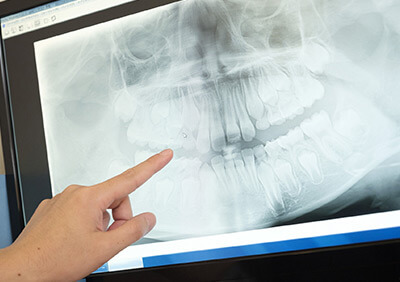

CTスキャン・精密検査にて

治療計画

インプラントの治療例

複雑なインプラント手術においてCTスキャン撮影は絶対に必要な検査です。

CTスキャンによって血管、神経、骨の状態を正確に判断する事ができます。